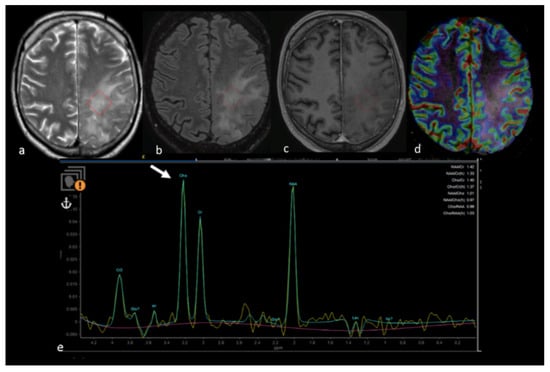

- Chiang, I.C.; Kuo, Y.T.; Lu, C.Y.; Yeung, K.W.; Lin, W.C.; Sheu, F.O.; Liu, G.C. Distinction between high-grade gliomas and solitary metastases using peritumoral 3-T magnetic resonance spectroscopy, diffusion, and perfusion imagings. Neuroradiology 2004, 46, 619–627. [Google Scholar] [CrossRef] [PubMed]

- Wijnen, J.P.; Idema, A.J.; Stawicki, M.; Lagemaat, M.W.; Wesseling, P.; Wright, A.J.; Scheenen, T.W.; Heerschap, A. Quantitative short echo time 1H MRSI of the peripheral edematous region of human brain tumors in the differentiation between glioblastoma, metastasis, and meningioma. J. Magn. Reson. Imaging 2012, 36, 1072–1082. [Google Scholar] [CrossRef] [PubMed]

- Hattingen, E.; Raab, P.; Franz, K.; Zanella, F.E.; Lanfermann, H.; Pilatus, U. Myo-inositol: A marker of reactive astrogliosis in glial tumors? NMR Biomed. 2008, 21, 233–241. [Google Scholar] [CrossRef]

- Kallenberg, K.; Bock, H.C.; Helms, G.; Jung, K.; Wrede, A.; Buhk, J.H.; Giese, A.; Frahm, J.; Strik, H.; Dechent, P.; et al. Untreated glioblastoma multiforme: Increased myo-inositol and glutamine levels in the contralateral cerebral hemisphere at proton MR spectroscopy. Radiology 2009, 253, 805–812. [Google Scholar] [CrossRef] [PubMed]

- Ricci, R.; Bacci, A.; Tugnoli, V.; Battaglia, S.; Maffei, M.; Agati, R.; Leonardi, M. Metabolic findings on 3T 1H-MR spectroscopy in peritumoral brain edema. AJNR Am. J. Neuroradiol. 2007, 28, 1287–1291. [Google Scholar] [CrossRef]